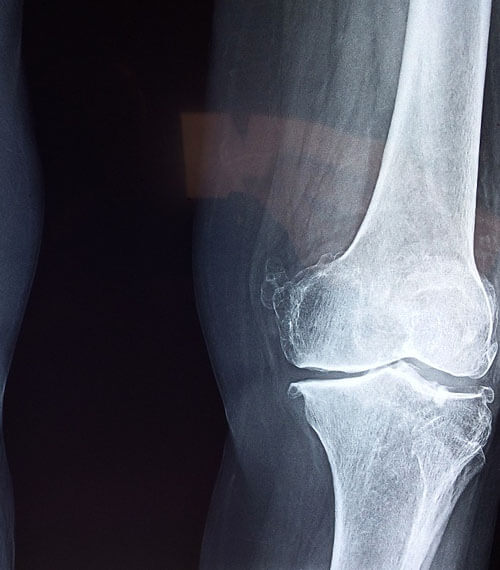

2. 퇴행성관절염

무릎을 많이 사용해 무릎 안쪽의 연골과

인대 등 주요 기관들이 닳아서 기능이 다하고

통증이 생기는 질환입니다.

해당 질환은 연골이 닳아서 없어지는 과정

이거나 없어진 이후이기 때문에

발생하고 초반엔 약물이나 물리치료 등의

비수술적 치료를 할 수 있지만

이미 많이 닳아서 없어진 경우라면

인공관절치환술, 무릎관절치환술 등의

수술적 치료가 진행될 수 있습니다.